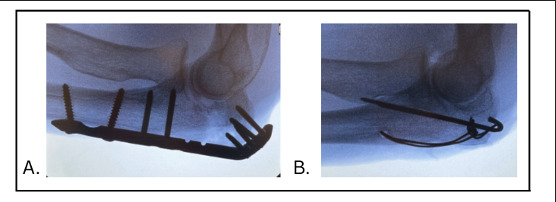

Olecranon fractures are often treated operatively, with treatment options commonly including but not limited to plate and screw fixation and tension-band wire fixation [Figure 1].3 Tension-band wiring has historically been indicated for minimally comminuted olecranon fractures without extension distally or involvement of the coronoid or shaft.4 It has had consistently good results, with 85% of patients reporting good or excellent results.5 However, tension-banding is known to cause hardware irritation, yielding meaningful removal rates.4,6 Alternatively, plate and screw fixation is a versatile fixation construct that can be used for simple as well as comminuted olecranon fractures and/or fractures with distal extension. Plate and screw fixation has also shown favorable outcomes.3,7

_plate_and_screws__and_(b)_tension-band_wiring.png)